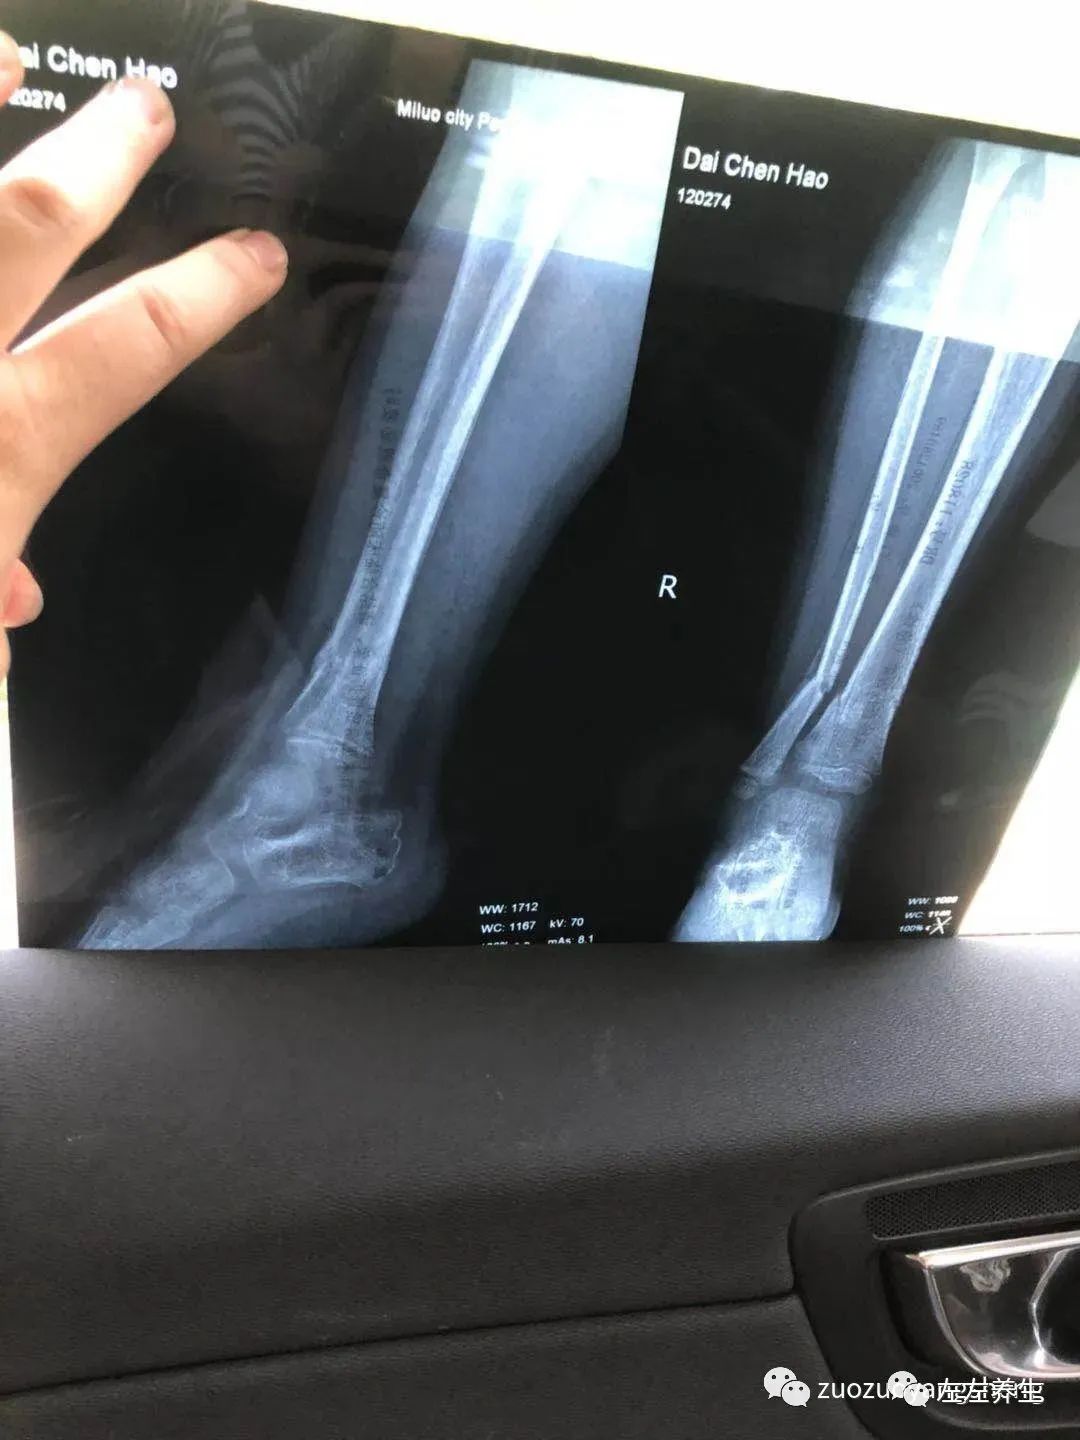

也许是感受到了我的变化,拍片子的时候他真的很乖。只是意外并不因为他的懂事而对他网开一面,结果显示右胫腓骨下端骨折、挨着的胫骨处有细微裂痕。

附骨折第一天检测单据:

附骨折第一周复查单据:

附检测单据:

孩子因为拆了石膏,安全感全失,吵闹了两天腿疼。同学说这个是正常现象,看了拍照发给他的片子后说,骨裂还是这么多要注意一下就好。